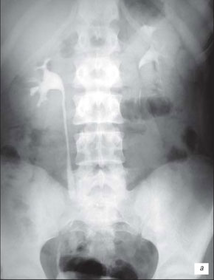

Висхідна цистографія

На даній рентгенограмі спостерігаємо активно-пасивний міхурово-сечовий рефлюкс зліва 4 ступені. Виражена дилатація чашечко-мисочкової системи, деформація чашок.

а – у фазі максимального наповнення сечового міхура, пасивний рефлекс; б – у фазі сечовипускання, активний рефлекс.